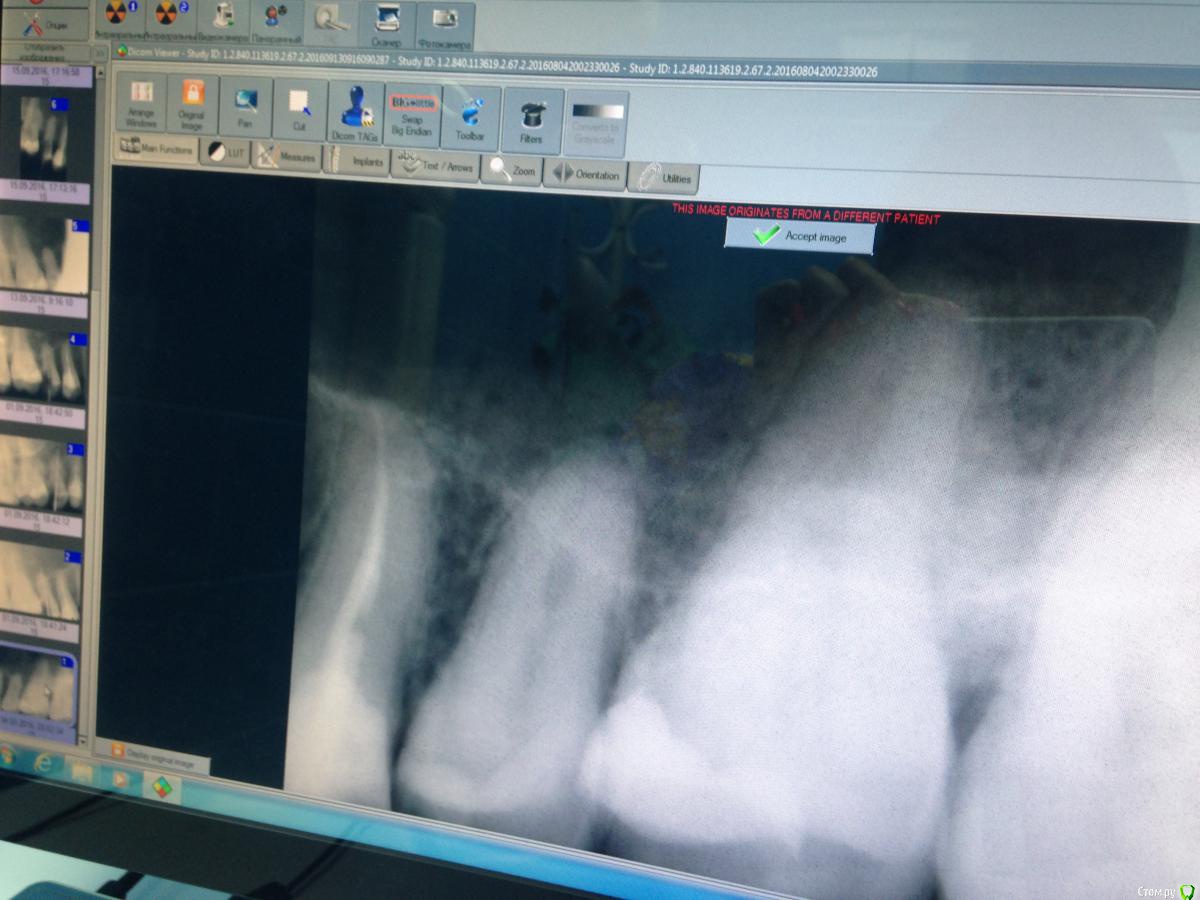

Malina11v Опубликовано 18 сентября, 2016 Поделиться Опубликовано 18 сентября, 2016 (изменено) Здравствуйте, хотела бы посоветоваться с коллегами. Такой случай: в начале июля приходила пациентка, ей другой доктор в нашей клинике поставила пломбы по глубокому кариесу на 15 и 16 зубы, через месяц она приходит еще к другой и говорит , что зуб болит уже месяц как, какой именно не знает, эта доктор принимает решение, что болит 15 и ставит депульпин. Через неделю пациентка приходит ко мне на обработку каналов, зуб Всю эту неделю ныл. В процессе обработки я расширяю канал до 40 и ставлю каласепт, Еще через неделю начинаю мыть парканом канал и пациенка указывает на резкую боль в области щеки и под глазом, понимаю что паркан зашел в пазуху, сразу начинаю мыть дистилированной водой обильно, ставлю крезофен и отправляю на неделю, так же пациенка указала на появление насморка, назначаю сосудосуживающие в нос и нимесил 5 дней, но гайморит у нее уже 10 лет как.Созваниваюсь с ней через пару дней , улучшения незначительные: зуб ноет, насморк есть, Назначаю сумамед 3 дня.через пару дней мою уже хлоргексином 2% и снова на каласепт. Через неделю: зуб эту неделю ныл, насморк немногл спал, но еще держится. Снова на каласепт и на две недели. Далее через две недели она приходит снова к другому врачу: зуб ноет , насморк есть, Приносит заключение ЛОРа с односторонним гайморитом , так же на снимках КТ определяется пломбировочный материал в пазухе и просвеь пазухи затемнен. Прилагаю снимки до лечения, во время обработки с инструментами и после пломбирования канала, На снимках с файлами в области верхушки видны белые тени, что это можеь быть? На кт их очень хорошо видно в виде полулунок, кроме каласепта и крезофена в каналах ничегл не было Изменено 18 сентября, 2016 пользователем Malina11v Ссылка на комментарий

Fibez Опубликовано 18 сентября, 2016 Поделиться Опубликовано 18 сентября, 2016 так может Вы нам КТ тогда и покажите? Раз их там хорошо видно? потому что тут кроме разбитой (резорбированной?) верхушки не видно ничего 1 Ссылка на комментарий

lightella Опубликовано 18 сентября, 2016 Поделиться Опубликовано 18 сентября, 2016 Каласепт - рентгеноконтрастный материал. Судя по тому, как разбит апекс, за верхушкой он и есть. 1 Ссылка на комментарий